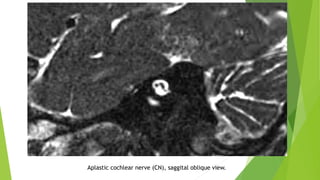

Hypoplastic cochlear nerve (CN), saggital oblique view.

3- Absent CN

There is no nerve in the anteroinferior part of the IAC.

This is definitely present in cochlear aplasia.

It can also be seen in CA hypoplasia and aplasia.

Aplastic cochlear nerve, axial view

Aplastic cochlear nerve (CN), saggital oblique view.